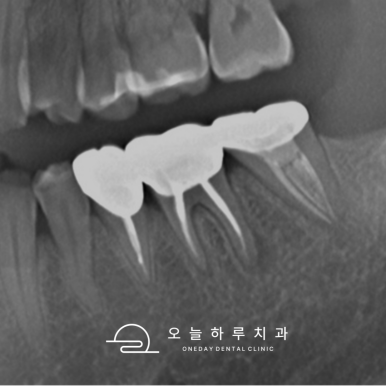

📸 케이스 1: #37 C-shape Re-Endo

- 통증 및 치아 흔들림 호소

- C-shape 근관 구조로 난이도 높은 케이스

- 여러 차례 소독 및 MTA 실러로 근관 충전

✅ 1년 후까지 안정적인 상태 유지